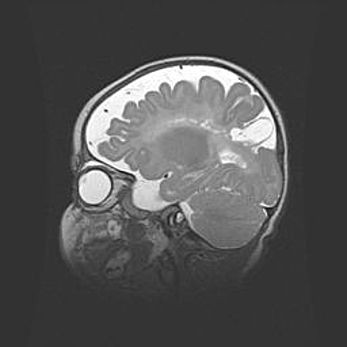

Мальформация Денди-Уокера. Киста задней черепной ямки.

Агенезия мозолистого тела.

Возраст: 2,5 месяца

Вес: 2420 г

Пол: женский

Окружность головы: 37 см

Срок гестации: 32 недели

Мальформация Денди—Уокера — редкий вид патологии ЦНС, представляющий собой врожденный порок развития каудального отдела ствола и червя мозжечка, ведущий к неполному раскрытию срединной (Мажанди) и латеральных (Лушка) апертур IV желудочка мозга. Для этогно синдрома характерна триада симптомов: гипотрофия червя мозжечка и/или полушарий мозжечка, кисты задней черепной ямки, гидроцефалия различной степени. В 70% случаев порок сочетается и с другими аномалиями головного мозга, в частности с агенезией мозолистого тела.